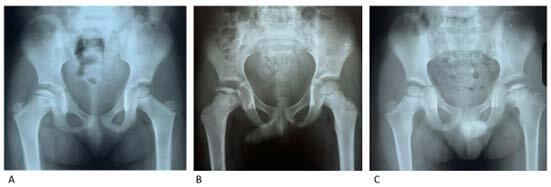

Results: We studied 20 patients with Meyer's dysplasia, representing 1.4% of LCPD cases in children. The majority were boys (85%) with symptom onset at 38 months. Claudication (25%) and mild pain (40%) were the main complaints. Radiographic findings showed a smaller, granular, or asymmetric nucleus. The average follow-up was 6.4 years, with interventional treatment in 5 cases. Most showed complete reossification and centralization of the femoral head.

Abstract Image